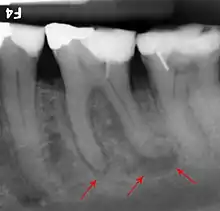

If disease is identified through this process, then a full periodontal analysis is performed, often by dental hygienists, oral health therapists or specialist periodontists. This involves full mouth periodontal probing and taking measurements of pocket depths, clinical attachment loss and recession. Along with this other relevant parameters such as plaque, bleeding, furcation involvement and mobility are measured to gain an overall understanding of the level of disease. Radiographs may also be performed to assess alveolar bone levels and levels of destruction.[41]